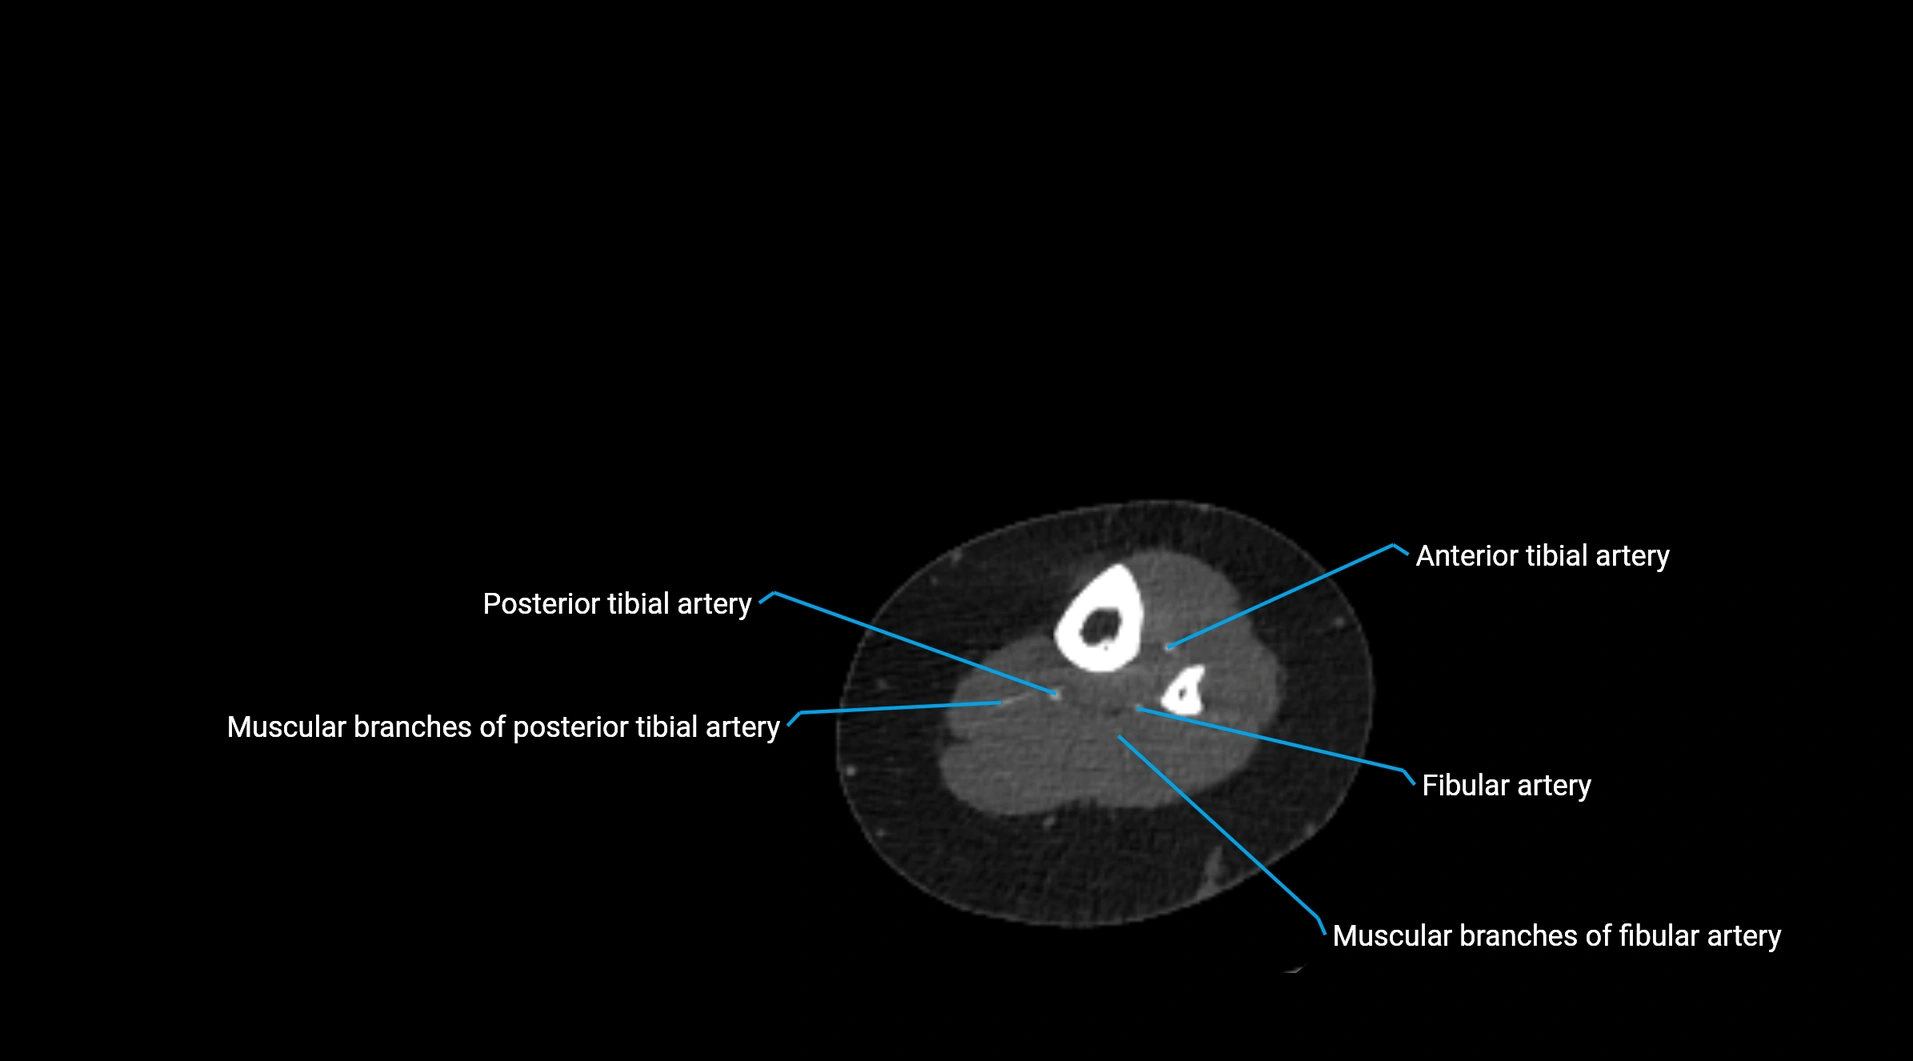

Contrast-enhanced CT (CTA):

• Gold standard for abdominal aortic imaging

• Provides excellent detail of lumen, wall, aneurysm, thrombus, and branch vessels

• Multiplanar and 3D reconstructions help in aneurysm measurement, stent graft planning, and dissection evaluation

• Detects acute rupture, traumatic injury, or occlusion with high sensitivity